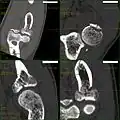

CT scan showing a radial head fracture

Radial head fractures are diagnosed from a clinical assessment and diagnostic imaging. Clinical assessment may include pain or tenderness at the radial head, bruising, swelling, and a limited range of motion of the injured elbow.[2] Diagnostic imaging may include ultrasound, plain radiography (x-ray imaging), Computed tomography scan (CT), and magnetic resonance imaging (MRI).[2][4] A fat pad sign may be present on diagnostic imaging and may indicate a radial head fracture.[5]